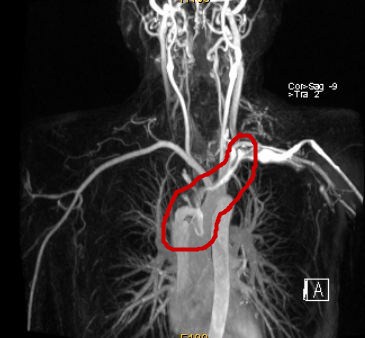

該院檢查發現腫瘤將近10cm大小,已經侵犯上腔靜脈,上腔靜脈、雙側頭臂靜脈及右側頸內靜脈內已經有癌栓並血栓形成,上腔靜脈已經無法通過影像看到,正是這些栓子導致張先生出現了頭暈、臉腫等上腔靜脈阻塞的癥狀。深圳市二醫院胸外科主任錢有輝教授仔細分析病情後指出,本例患者主要問題在於患者的胸腺瘤已經出現了大血管侵犯,手術需要完整切除腫瘤之外還需要對部分大血管進行切除並置換人工血管,這樣才能達到斬草除根的效果。

腫瘤阻塞了上腔靜脈,血流受阻,造影不能顯現